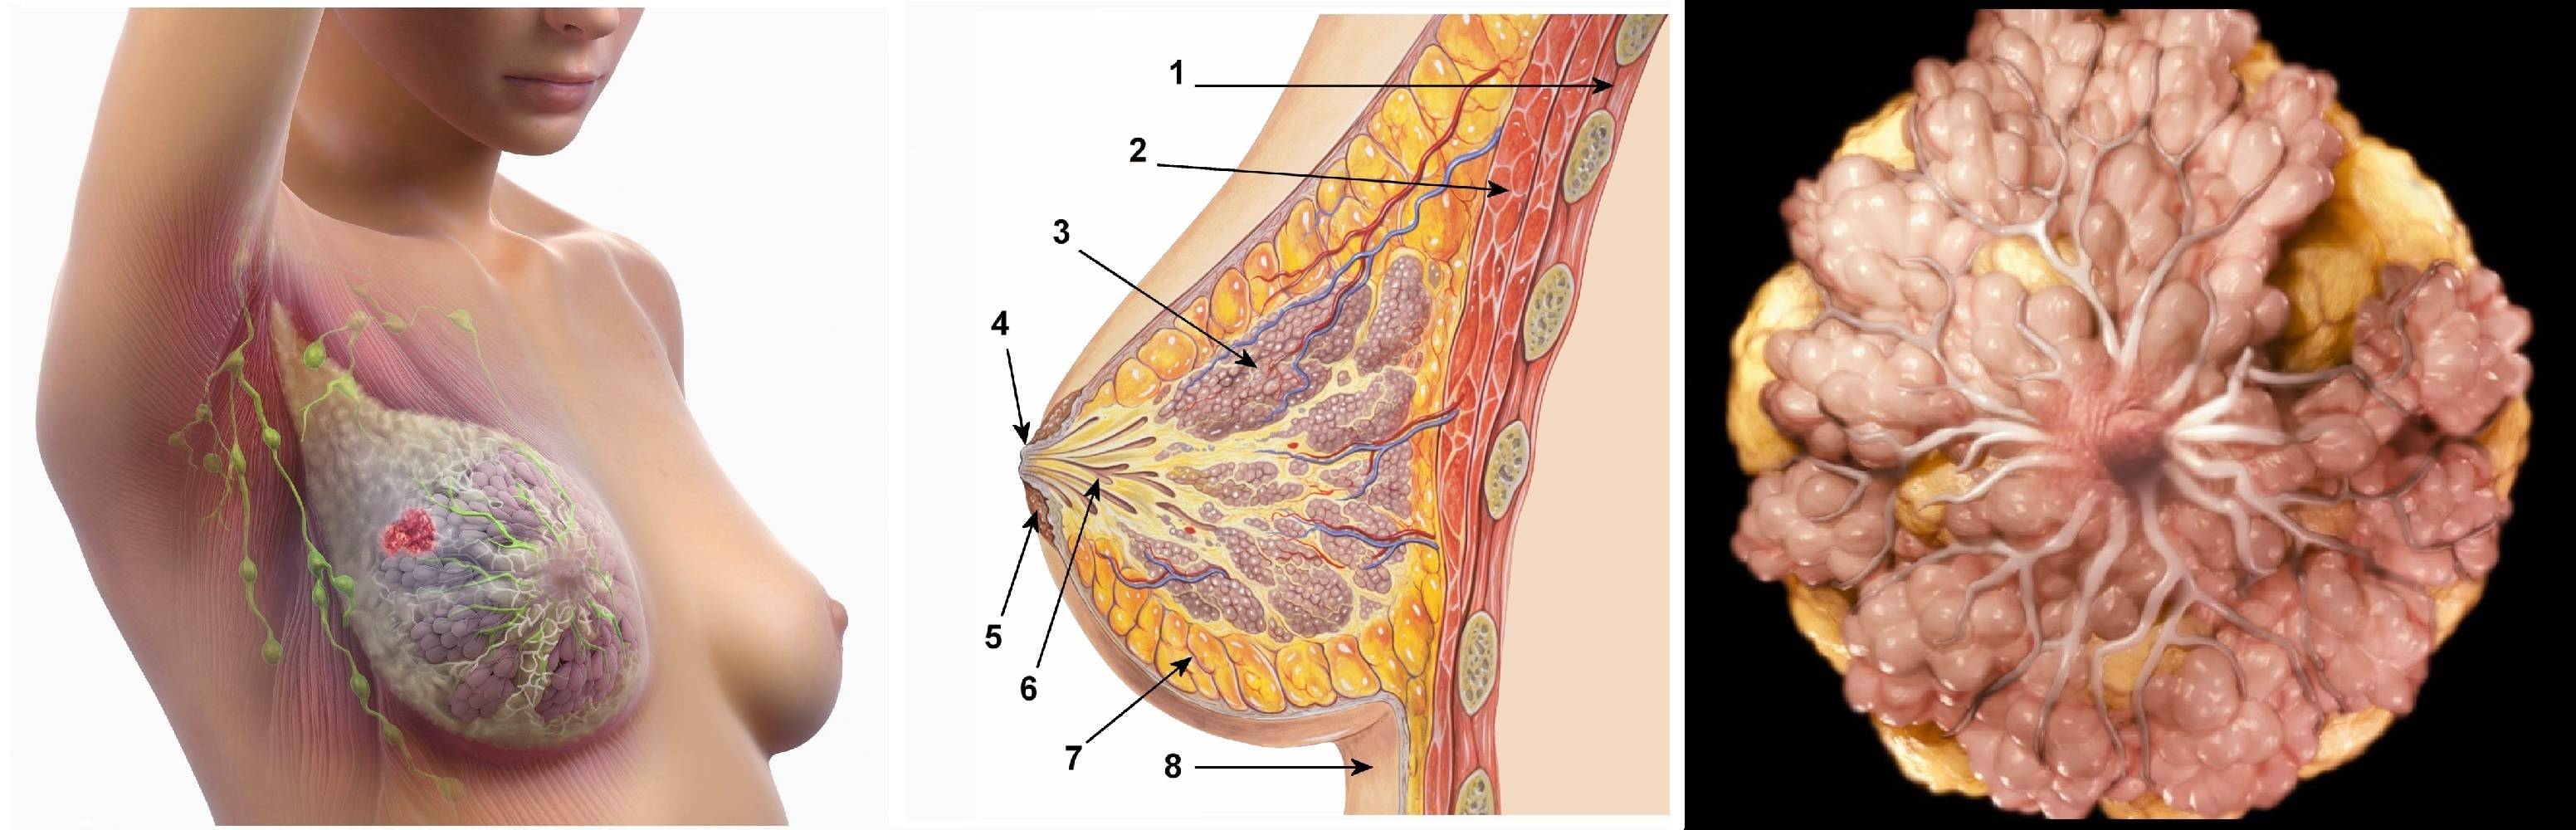

Фото раковой шишки на теле

Раковые шишки могут возникать не только на лице, но и на других частях тела. На фотографиях вы можете увидеть примеры раковых шишек на шее, руках, ногах и туловище. Обратите внимание на различные формы и размеры раковых шишек, а также на их внешний вид.